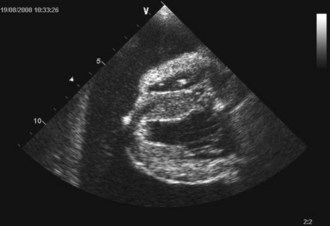

An intravenous catheter was placed into a cephalic vein and blood obtained via the catheter for an emergency database that was unremarkable. Continuous electrocardiogram monitoring was commenced and sinus tachycardia identified. Echocardiography confirmed the clinical suspicion of pericardial effusion (Figure 31.4).

Figure 31.4 Echocardiogram image of pericardial effusion visible as an anechoic space around the heart; both a collapsed right ventricle and the left ventricle are also visible.

(Photograph courtesy of Tobias Wagner)